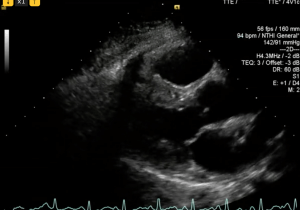

A 40 year old man presents with near syncopal events and has low oxygen saturations in the emergency department, on a past history of systemic hypertension. His blood pressure is low-normal and the chest X ray is clear, so he goes on to have an urgent CTPA which shows bilateral PE with a large burden of clot in both the left and right main pulmonary artery. Low dose thrombolysis is considered to minimise the risk of long term pulmonary hypertension. The patient is transferred to ICU and an urgent echo is performed to assess the right ventricle.

Here are the first loops, can you spot any subtle pathology on these initial scans?

Looking at the ventricle in short axis, the septum may bow towards the LV which will form a D shape in diastole, producing a “volume overloaded right ventricle” appearance.

Only later when the RV has been trained will it be able to generate higher pressures. If the LV is D shaped in systole, this is a “pressure overloaded right ventricle”.

Acute cor pulmonale with both pressure AND volume overload (D shape in systole AND diastole) is often absent.